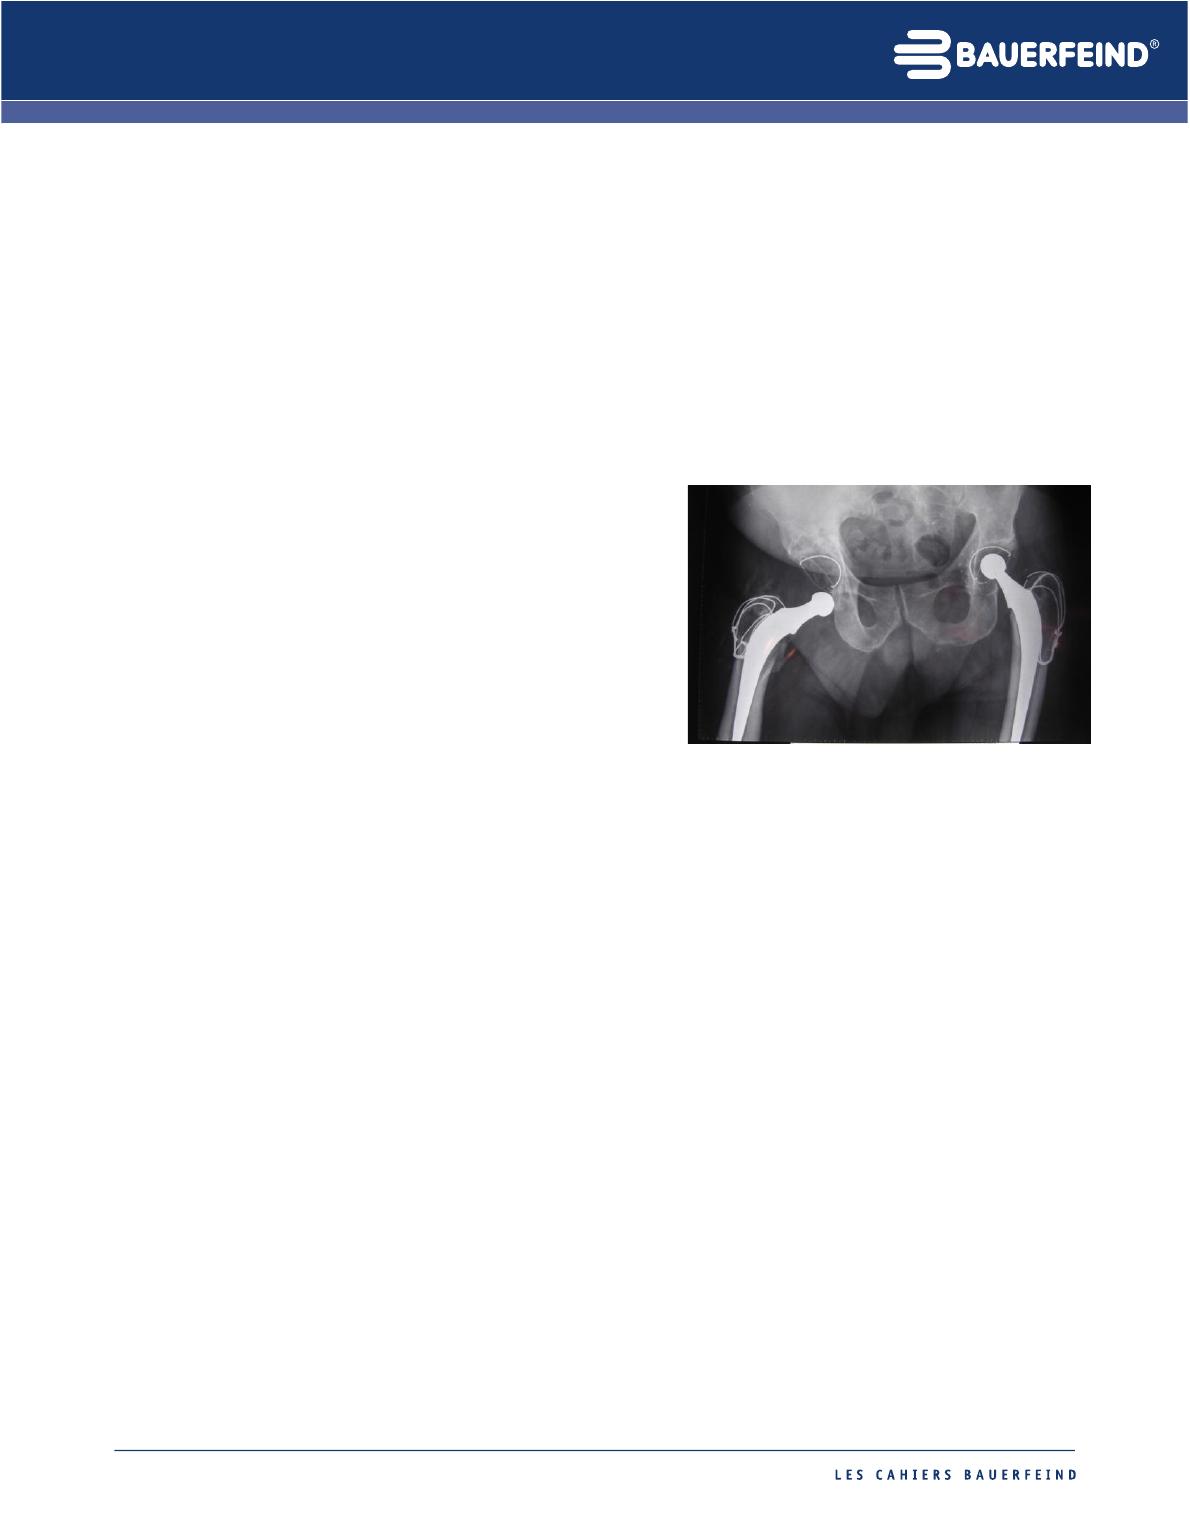

Figure 1 : luxation survenue pour la première fois 19 ans après

l’intervention. On pense que les débris liés au polyéthylène

utilisé sont responsables de cette

luxation tardive.